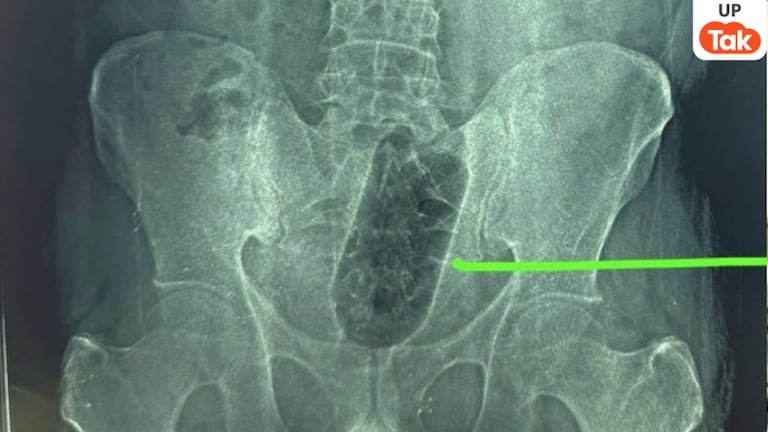

आगरा में इस युवक ने मलाशय में डाल ली एक लीटर वाली प्लास्टिक बोतल! फिर 36 घंटों तक रहा बेचैन

UP News: आगरा के एक युवक ने अपने मलाशय में 1 लीटर की प्लास्टिक बोतल डाल ली. ये बोतल अंदर फंस गई. इसके बाद युवक की जिंदगी काफी घंटों के लिए नर्क बन गई.

UP News: आगरा की साकेत कॉलोनी में रहने वाला एक युवक 36 घंटे से दर्द में था. शुरू में उसने किसी को कुछ नहीं बताया. मगर जब दर्द असहनीय होने लगा तो उसके परिवार ने उसे रोते हुए देख लिया. फिर परिजन उसे फौरन अस्पताल लेकर गए. यहां डॉक्टरों को जो पता चला, वह हैरान कर देने वाला था.